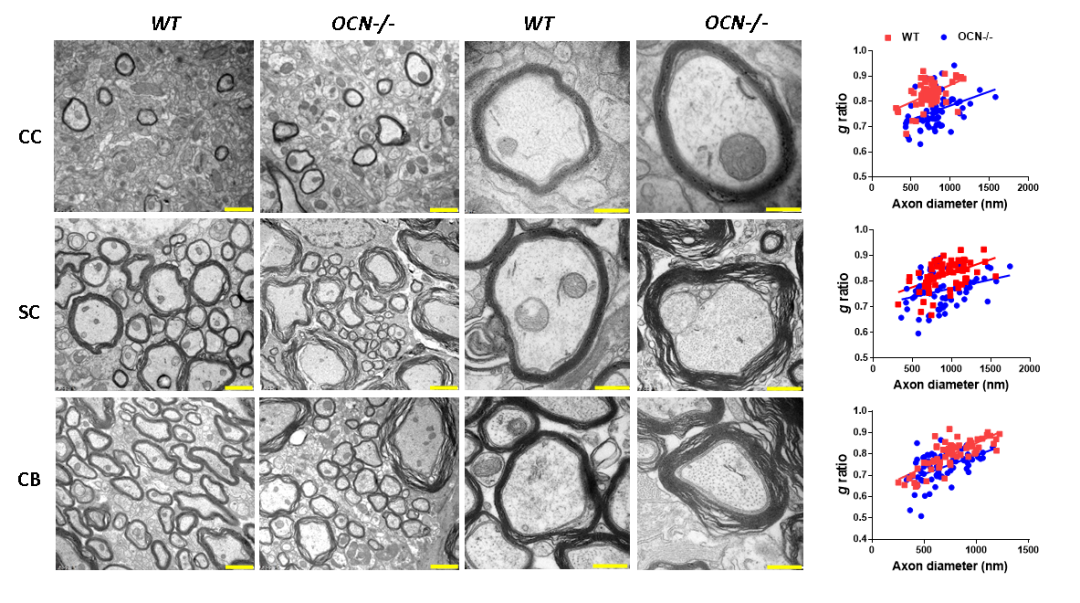

为了知道骨钙素OCN是否对中枢神经系统胶质细胞具有调节作用,团队采用OCN基因敲除的小鼠进行研究,基于免疫染色发现:OCN敲除后小鼠中枢系统白质区域髓鞘相关marker基因表达增加,然后利用蛋白杂交进行验证;而通过电镜分析发现OCN基因敲除后髓鞘厚度增加,进一步确认了OCN对少突胶质细胞具有调控作用。

图2. 电镜分析野生型和骨钙素基因敲除鼠白纸区域(包括胼胝体、脊髓和小脑)中髓鞘变化。左四是代表性电镜图片,右一是g-ratio和轴突相关分析 。